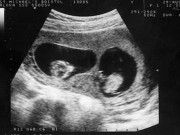

1. Hãy để ý biểu cảm khuôn mặt ông xã khi bác sỹ chẩn đoán bạn mang thai đôi.